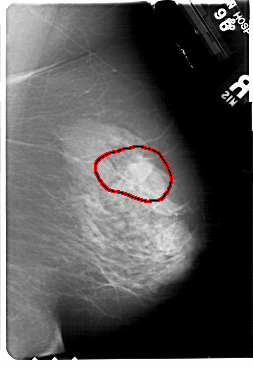

FILE: A_1720_1.LEFT_CC.OVERLAY

TOTAL_ABNORMALITIES 1

ABNORMALITY 1

LESION_TYPE MASS SHAPE ARCHITECTURAL_DISTORTION MARGINS SPICULATED

ASSESSMENT 2

SUBTLETY 5

PATHOLOGY BENIGN_WITHOUT_CALLBACK

TOTAL_OUTLINES 1

BOUNDARY